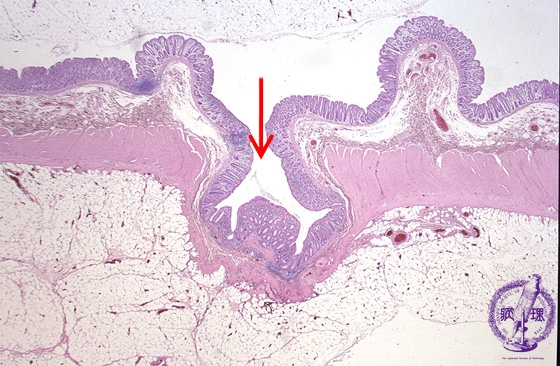

- 9.Small intestine, Large intestine

- (2)Diverticulosis of large intestine (diverticulitis) >

Microscopic view (H&E stain, low power): Both mucosa and the underlying muscularis propria protrude through the external bowel wall.

Click the image to see the enlarged image.